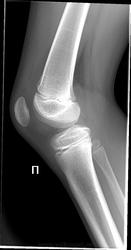

1.Левена болезнь (A. Läwen, 1876—1958, нем. хирург) —остеохондропатия надколенника; проявляется болью при надавливании на надколенник или при его смещении.

2.Асептический некроз коленной чашечки / Sinding-Larsen-Johansson disease

Описание и характеристика. Этот синдром относится к остеохондрозам. Поражается сухожилие и коленная чашечка. Развивается отек и болезненность данного сустава.

Клиника, диагностика и лечение. Может наблюдаться костная фрагментация нижней части чашечки. Это, как правило, результат травмы или контузии чашечки. Процесс может закончиться кальцификацией не месте воспалительного повреждения. Прогноз, в целом, благоприятен.

Ларсена болезнь видел на нашем сайте. Кто-то задавал вопрос. Там был кажется исход, выглядело как несросшийся апофиз у вершины надколенника (нижний полюс). Изменений Левена не представляю. Не может это оказаться остеомиелитом? Алексей Станиславович, вы кажется УЗИ занимаетесь, может посмотрите?